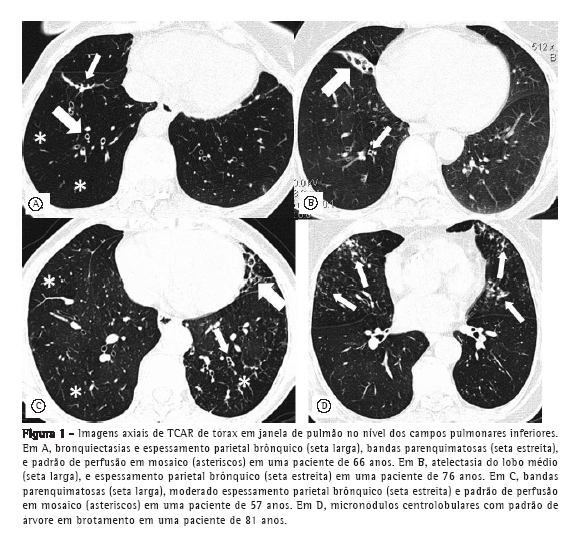

As mulheres com DPOC apresentavam, com maior frequência e diferenças estatisticamente significantes, as seguintes alterações tomográficas: bronquiectasias, padrão de perfusão em mosaico, atelectasia linear (lobar em uma paciente) e padrão de árvore em brotamento. Não foi identificado enfisema panlobular. As lesões predominaram nos lobos inferiores (Tabela 2 e Figura 1).

Após o pareamento, o grupo DPOC apresentou as seguintes alterações tomográficas com diferenças estatisticamente significantes em relação ao grupo controle: bandas parenquimatosas, espessamento das paredes brônquicas, bronquiectasias, perfusão em mosaico e atelectasias laminares. Essas alterações predominaram nos campos pulmonares inferiores, com distribuição no campo inferior, em 76,6%; no campo médio, em 15,6%; e no campo superior, em 7,8%. (Tabela 4).